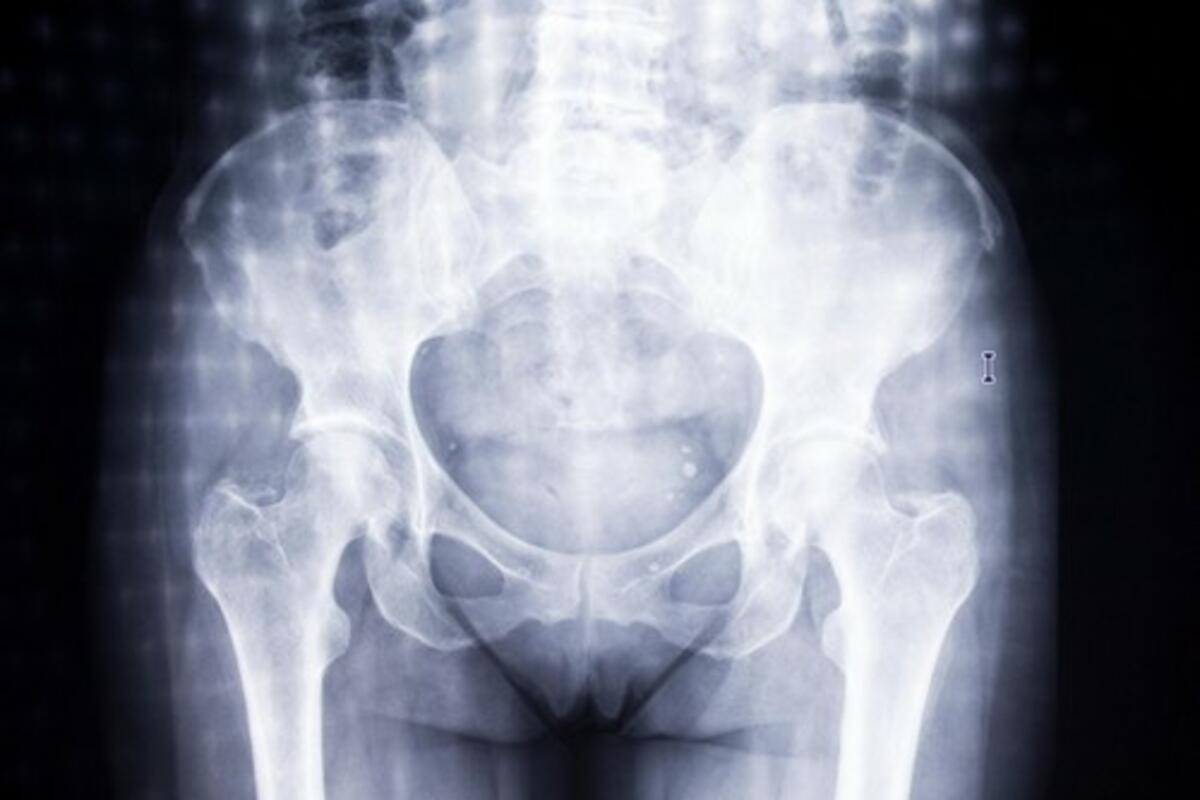

Od žena koje sve jedu, do onih koje konzumiraju samo ribu ili onih kojima je meso povremeno na meniju, vegetarijanke su bile jedina grupa sa povećanim rizikom od preloma kuka.

Vegetarijanke, žene koje su izbacile meso iz svoje ishrane ili ga nikada nisu ni jele, imaju 33 odsto veći rizik od preloma kuka u poređenju sa onima koje konzumiraju meso, otkrila je studija naučnika sa University of Leeds, sprovedena na više od 26.000 žena srednjih godina u Velikoj Britaniji.

Među 26.318 žena, koje su u vreme kada su odabarane za studiju bile u dobi od 35 do 69 godina, 822 slučaja preloma kuka su primećena tokom 20 godina studija – što je predstavljalo nešto više od 3 odsto populacije posmatranog uzorka. Nakon prilagođavanja faktorima kao što su pušenje i godine starosti, vegetarijanke su bile jedina grupa sa povećanim rizikom od preloma kuka. Ova studija je jedna od retkih koja upoređuje rizik od preloma kuka kod vegetarijanaca i mesojeda gde je pojava preloma kuka potvrđena na osnovu bolničke dokumentacije. Naučnici naglašavaju da postoji potreba za dodatnim istraživanjem tačnih uzroka zašto su vegetarijanke u većem riziku od preloma kuka.